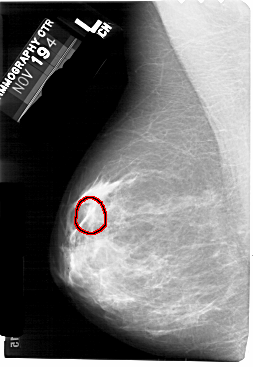

A_1556_1.LEFT_MLO

FILE: A_1556_1.LEFT_MLO.OVERLAY

TOTAL_ABNORMALITIES 1

ABNORMALITY 1

LESION_TYPE MASS SHAPE OVAL MARGINS OBSCURED

ASSESSMENT 4

SUBTLETY 2

PATHOLOGY BENIGN

TOTAL_OUTLINES 1

BOUNDARY